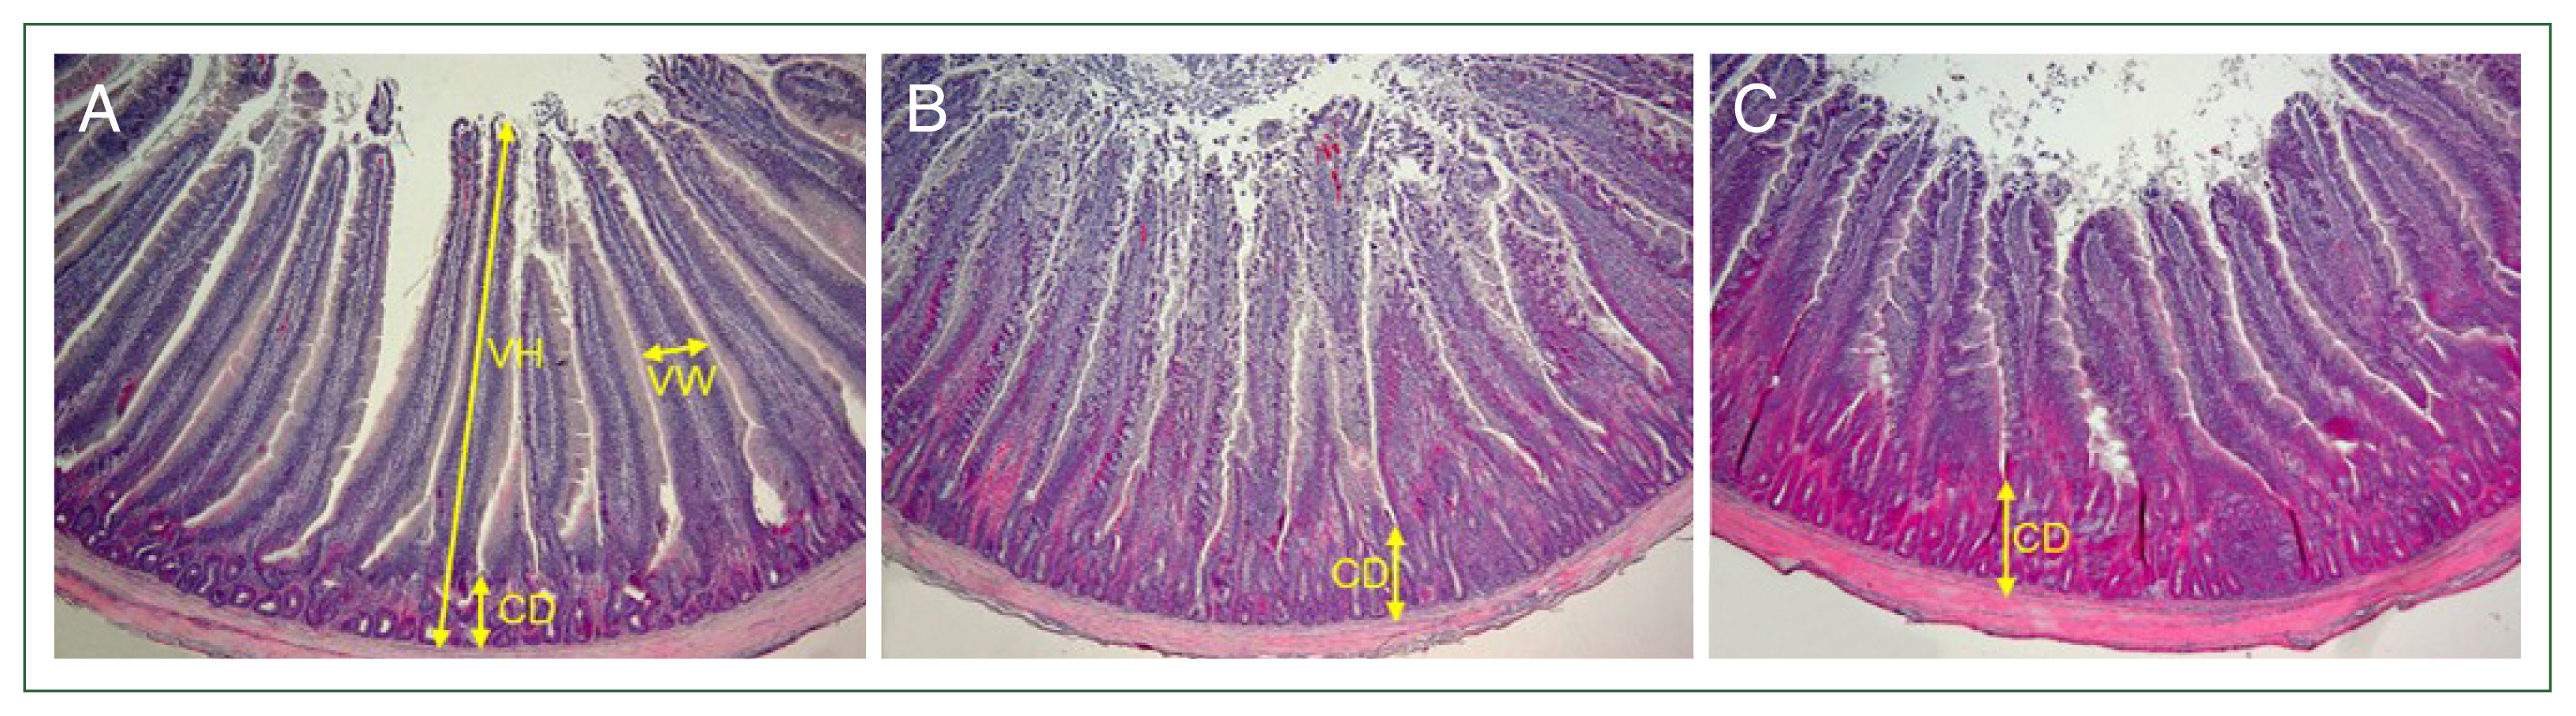

Poultry coccidiosis, caused by 7 Eimeria species, has a significant economic impact on the poultry industry and is managed mainly by chemotherapeutic drugs. However, alternative control measures are needed due to the emergence of drug-resistant strains. This study aimed to evaluate the anticoccidial effects of a multicomplex mineral-based diet in broilers infected with Eimeria acervulina. Broilers were fed a multicomplex mineral-based diet and infected with E. acervulina. Fecal oocyst shedding was 39.0% lower in the E. acervulina-infected broilers treated with the multicomplex mineral compared to that in untreated-infected broilers (365.7×106±45.7 versus 599.8×106±8.7, P<0.05). On day 6 post-infection, body weight gain was significantly higher in treated-infected chickens than untreated chickens (103.2±1.5% versus 94.1±1.7%, P<0.001). The lesion scores were similar between the 2 groups. Histopathological observations revealed that the width of the villi in the treated-infected chickens (286±9.5 μm) was significantly increased by 19.1% (240±10.8 μm, P<0.05) and 34.9% (212±7.3 μm, P<0.001) compared to those in the untreated-uninfected and untreated-infected groups, respectively. However, the villous height and crypt depth were similar between the untreated- and treated-infected groups. The positive effects of the dietary multicomplex mineral, including reduced fecal oocyst shedding, increased weight gain, and increased villi width, suggest its potential application in mitigating the adverse effects of Eimeria infection in both conventional and organic chicken industries.